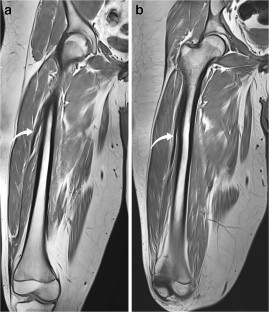

All patients presented with progressive unilateral restricted knee flexion and had multiple imaging studies targeting the knee before diagnosis. Diagnosis in all patients was made on MRI of the thighs, which demonstrated a fusiform low signal intensity structure with muscle-like architecture arising from the anterior or anterolateral proximal femur and blending with the common quadriceps tendon distally. All patients underwent surgical release of the anomalous band with significant functional improvement.

Fig. 2